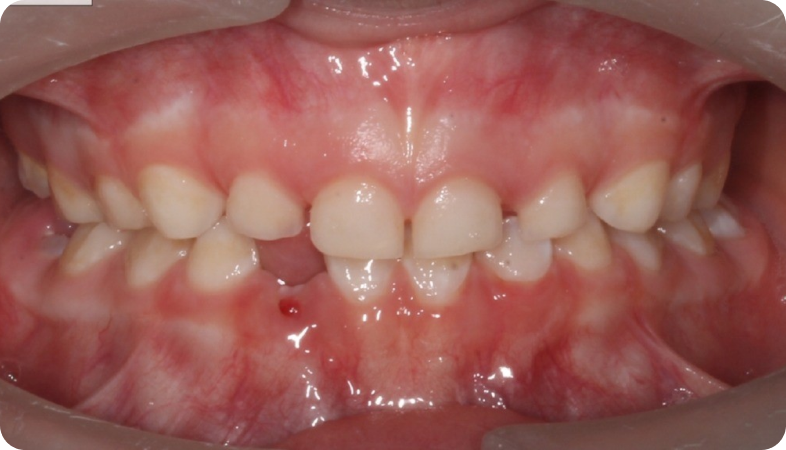

Cas cliniques